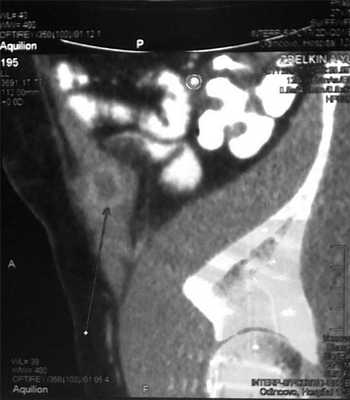

При ультразвуковом исследовании брюшной полости в правой подвздошной ямке определяется изоэхогенное образование 8х4 см с гипоэхогенными включениями, окруженное капсулой; определение экстра- или интраперитонеальной локализации образования оказалось затруднительным. При компьютерной томографии брюшной полости в правой подвздошной области, в тканях передней брюшной стенки наиболее вероятно - предбрюшинно определяется объемное образование 8,0х4,5 см с капсулой и очагами пониженной плотности. Клинический диагноз: Абсцедирующая гранулема послеоперационного рубца передней брюшной стенки, состояние после аппендэктомии; Сorpus alienum-?

Абсцедирующая межмышечная гранулема (лигатурный абсцесс) послеоперационного рубца передней брюшной стенки.